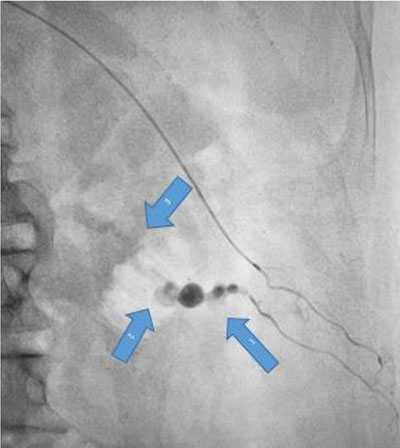

Urgent digital subtraction angiography (DSA) was done through right femoral access. The aortic angiogram showed no pseudoaneurysm or contrast extravasation from the left renal artery. However, the left lumbar artery at the L2 level showed a pseudoaneurysm with fistulous communication with the renal vein along the biopsy tract with contrast leak on delayed figures (Figure 1 and Figure 2).

Figure 1: Pseudoaneurysm in the intercostal branch of the lumbar artery at L2 level.

Figure 2: Pseudoaneurysm in the L2 lumbar artery (Arrowhead at 5 o’clock). A fistula formed between lumbar artery’s intercostal branch and the renal vein (Arrowhead at 7 o’clock). Flow of blood into renal vein directly from lumbar artery aneurysm (Arrowhead at 9 o’clock).